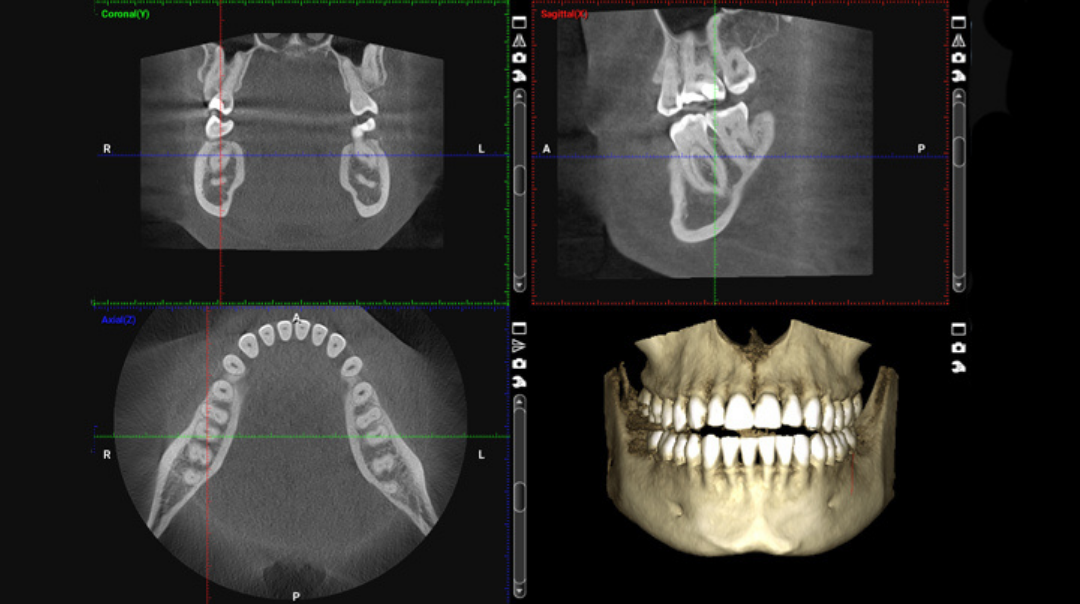

Tomografía Cone Beam (CBCT) y FaceScan 3D

En Imagen Lux, trabajamos con el tomógrafo CS 9600 de Carestream Dental, uno de los más avanzados del mercado y uno de los pocos disponibles en la región Caribe. Este equipo combina tomografía 3D, escaneo facial y múltiples campos de visión en una sola unidad compacta, lo que nos permite adaptarnos a las necesidades de cada especialista.

La tomografía (CBCT), en cambio, ofrece

imágenes tridimensionales con mayor

precisión, ideales para diagnósticos

complejos y planificación quirúrgica.

Contamos con el Carestream CS 9600,

uno de los tomógrafos más avanzados del

mercado, con capacidades 3D, múltiples

campos de visión y funciones como

FaceScan, que permite capturar estructuras

óseas y faciales con altísima definición y

menor exposición a radiación.